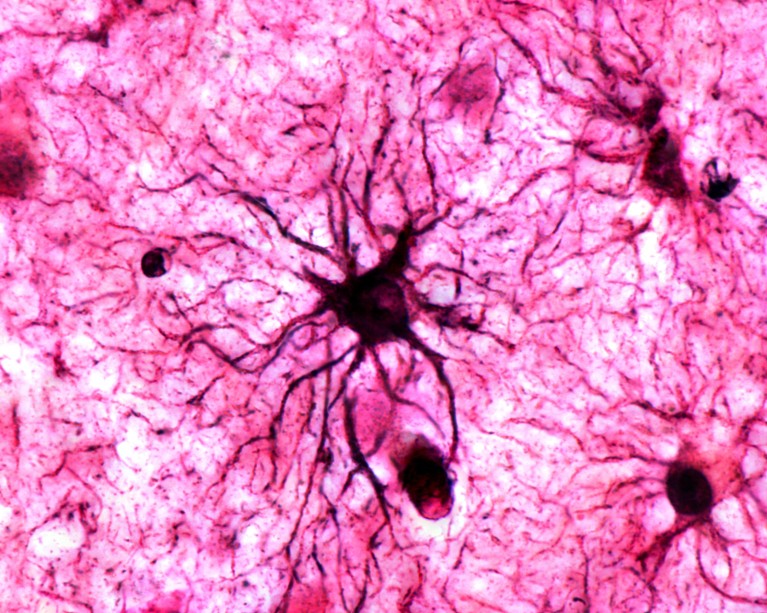

A type of brain cell called astrocytes play a crucial role in stabilizing memories in the brain.Credit: Jose Calvo/SPL

Astrocytes were thought to simply support neurons in creating the physical traces of memories in the brain, but the study found that they have a much more active role — and can even be directly triggered by repeated emotional experiences. The researchers behind the finding suggest that the cells could be a fresh target for treating memory conditions such as those associated with post-traumatic stress disorder and Alzheimer’s disease.

Nagai and his colleagues focused on the question of memory stabilization: how a short-term memory becomes more permanent in the brain. Previous research had found physical traces of memories in neuronal networks in brain regions such as the hippocampus and amygdala2. But it was unclear how these ‘engrams’ were stored in the brain as lasting memories after repeated exposure to the same stimulus.